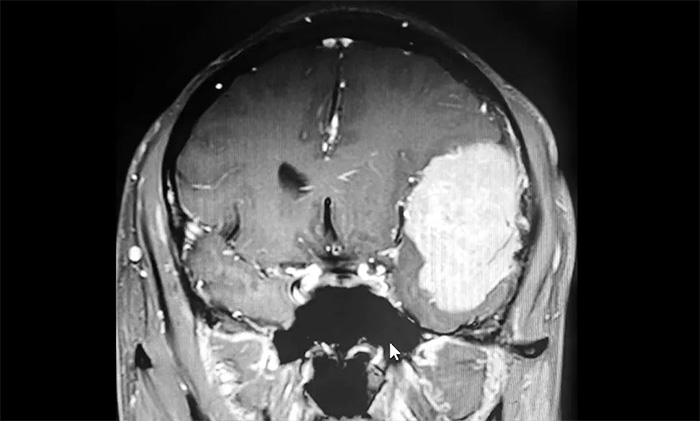

家人將其送往當(dāng)?shù)蒯t(yī)院,經(jīng)檢查,肩胛骨骨折。進(jìn)一步檢查頭顱CT,發(fā)現(xiàn)其左側(cè)額顳部團(tuán)塊狀高密度影,最大直徑約6.0公分(厘米)。病灶體積巨大,患者來(lái)到上海藍(lán)十字腦科醫(yī)院尋求進(jìn)一步治療。

入院后,患者收治于神經(jīng)內(nèi)科4A病區(qū)。完善針對(duì)性檢查后,經(jīng)多學(xué)科綜合會(huì)診,患者左側(cè)額顳部實(shí)性占位,最大直徑約6.0公分,體積如鴨蛋大小,考慮左側(cè)額顳部腦膜瘤。

▲ 腫瘤體積如鴨蛋大小

發(fā)生于額顳部位的巨大腦膜瘤,治療方法主要為顯微外科手術(shù)切除。該腫瘤不僅體積巨大,橫跨多個(gè)重要腦功能區(qū),行DSA檢查發(fā)現(xiàn),腫瘤包裹纏繞多根重要的動(dòng)脈血管,血供十分豐富。若直接行手術(shù)切除腫瘤,容易因術(shù)中大出血而危及患者生命。